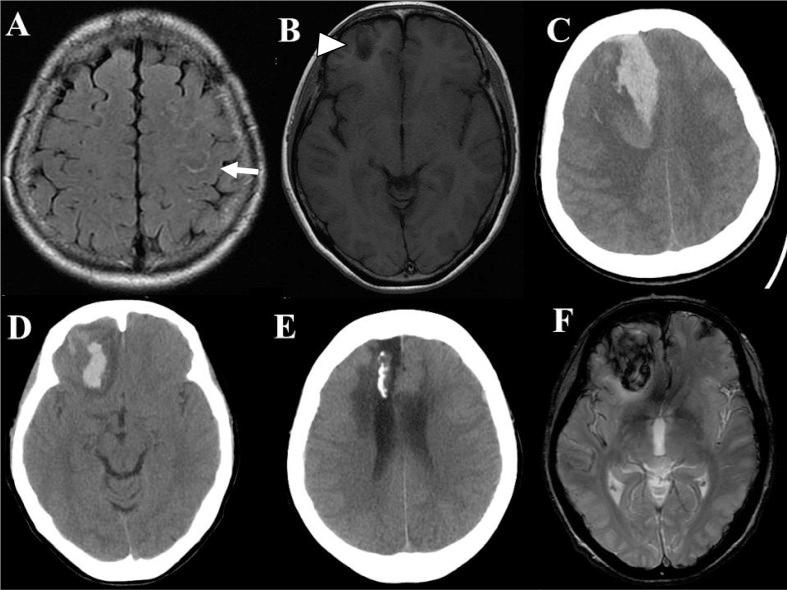

Cerebral amyloid angiopathy (CAA) is observed in most cases of nonhypertensive subcortical hemorrhage involving elderly patients. We herein describe the case of a female in whom a convexal subarachnoid hemorrhage was observed at 55 years of age. The cerebral hemorrhage occurred repeatedly; however, no obvious vascular lesions were observed on a cerebral angiography, and no signs of microbleeding or lesions in the deep white matter were identified on magnetic resonance imaging (MRI). Partial excision of the right frontal cortex and hematoma evacuation were performed, and histopathological examination showed deposition of an acidophilic substance with positive staining for Direct Fast Scarlet (DFS) in the cerebral vascular wall. Finally, brain hemorrhage due to CAA was diagnosed. This case suggests that CAA is an important differential diagnosis in patients with localized non-aneurysmal subarachnoid hemorrhage in the convexity sulcus.

脑淀粉样血管病(CAA)在大多数涉及老年患者的非高血压性皮质下出血病例中均可观察到。我们在此描述一例55岁女性患者,其脑凸面蛛网膜下腔出血。脑出血反复发生;然而,脑血管造影未观察到明显的血管病变,磁共振成像(MRI)也未发现微出血迹象或深部白质病变。进行了右额叶皮质部分切除术及血肿清除术,组织病理学检查显示脑血管壁有嗜酸性物质沉积,对直接耐晒猩红(DFS)染色呈阳性。最终,诊断为CAA所致脑出血。该病例提示,CAA是脑沟凸面局限性非动脉瘤性蛛网膜下腔出血患者的重要鉴别诊断。